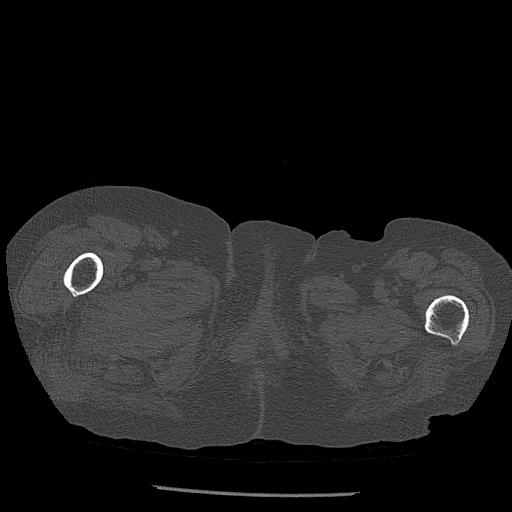

100703 1/27 両股正面+軸 1/29 両股正面+軸 94歳女性 パンソンロン